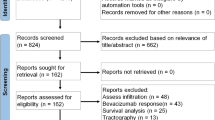

A systematic search of the four databases led to the identification of 216 studies. After checking for duplicates, 88 studies remained. Of these, 65 were excluded based on the pre-defined inclusion and exclusion criteria by reading titles and abstracts. The remaining 23 articles were selected for full-text evaluation. Following a detailed assessment, 3 studies were excluded owing to lack of analytical data for DKI and 1 study was excluded because it did not answer any of the two pre-defined review questions. Finally, 19 studies were deemed to be eligible for inclusion in the systematic review [9, 18,19,20,21,22,23,24,25,26,27,28,29,30,31,32,33,34,35]. For the primary question, investigating the role of DKI in glioma grading 17 studies was selected [9, 20,21,22,23,24,25,26,27,28,29,30,31,32,33,34,35]. For the secondary question, assessing the technique’s potential in differentiating glioma from other intra-axial tumours the remaining 2 studies was selected [18, 19]. The results of the selection process are presented in Fig. 1. The studies with their characteristics in the areas of histologic types of glioma, details of DKI acquisition technique (e.g. TR/TE, b values and diffusion encoding directions), DKI processing and post-processing (e.g. software used and extracted parameters) are illustrated in Table 1.

Seventeen studies addressed the first question and the results of quality assessment are summarized in Fig. 2 and Table 2 [9, 20,21,22,23,24,25,26,27,28,29,30,31,32,33,34,35]. For risk of bias, the quality was variable across each domain. In the patient selection domain, 10 were judged to be at low risk [9, 20,21,22, 26, 30,31,32,33,34,35] and 7 were considered high risk [23,24,25, 27,28,29]. In the index test domain, 9 studies were considered low risk whilst the remaining 8 were unclear in risk. For the reference standard domain, all studies were deemed low risk. Regarding flow and timing, 11 studies had low risk, 2 studies had high risk and 4 studies had unclear risk. For applicability, all studies across all domains were considered low risk.